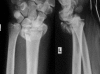

Background: A possible difficulty in intra-articular fracture of the distal radius is the displacement tendency of the radial styloid process due to the tension of the brachioradialis tendon.

Methods: Ten patients treated within one year for complex distal radius fractures by double-plating technique with a radial buttress plate and volar locking plate, through a single volar approach, were followed prospectively during 24 months. Outcome measures included radiographic follow-up, range of motion, grip strength and score follow-up (VAS, Gartland-Werley score and patient-rated wrist evaluation).

Results: Ten patients with intraarticular distal radius fractures with dislocation of the radial styloid process were treated with this technique. This resulted after 24 months in good clinical outcome (mean visual analog scale 0.9; almost symmetric range of motion; mean Gartland-Werley score 2 +/- 3; mean patient-rated wrist evaluation 3.2 +/- 2.4). Radiologic evaluation according to the Dresdner Score revealed anatomic reduction without secondary dislocation during the follow-up and uneventful consolidation.

Conclusions: The described technique strongly facilitates anatomic reduction and stable fixation of intra-articular distal radius fractures with dislocation of the radial styloid process and leads to satisfactory clinical and radiographic outcome.